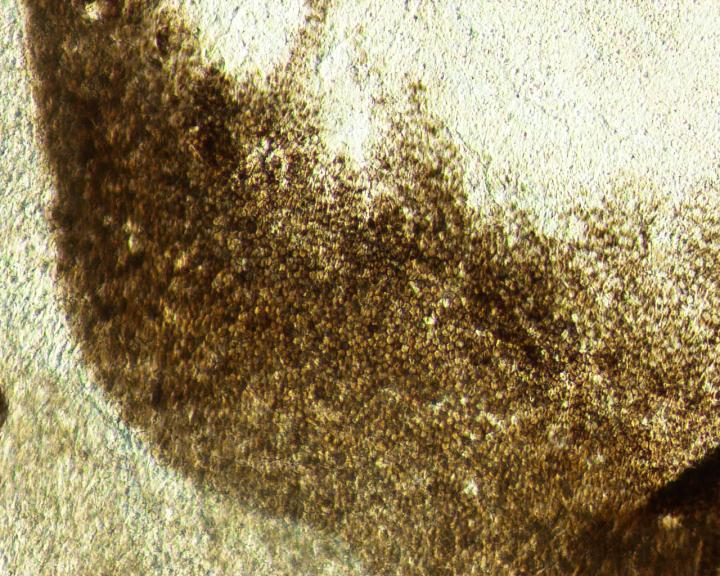

image: The cells at the edge of the pigmented cluster displayed typical morphology of hRPE cells with light, medium, dark pigmentation status. view more

Credit: CHA Biotech Co., Ltd.